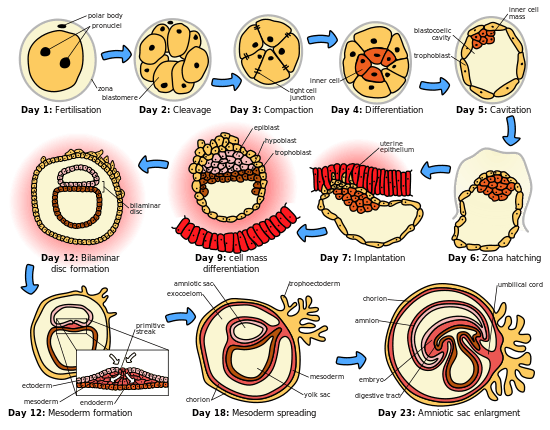

Development

The placenta begins to develop upon implantation of the blastocyst into the maternal endometrium. The outer layer of the blastocyst becomes the trophoblast, which forms the outer layer of the placenta. This outer layer is divided into two further layers: the underlying cytotrophoblast layer and the overlying syncytiotrophoblast layer. The syncytiotrophoblast is a multinucleated continuous cell layer that covers the surface of the placenta. It forms as a result of differentiation and fusion of the underlying cytotrophoblast cells, a process that continues throughout placental development. The syncytiotrophoblast (otherwise known as syncytium), thereby contributes to the barrier function of the placenta.

The placenta grows throughout pregnancy. Development of the maternal blood supply to the placenta is complete by the end of the first trimester of pregnancy (approximately 12–13 weeks).